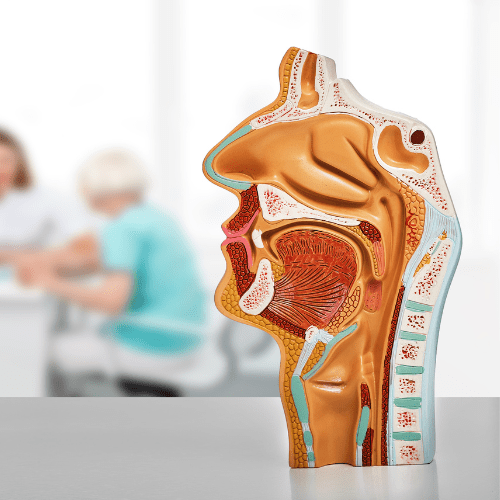

ENT

Our ENT specialists at Heal and Health Hospitals offer diagnosis and treatment for ear, nose, and throat conditions. Whether it’s sinus issues, hearing problems, or throat infections, we deliver expert care with advanced tools and techniques.